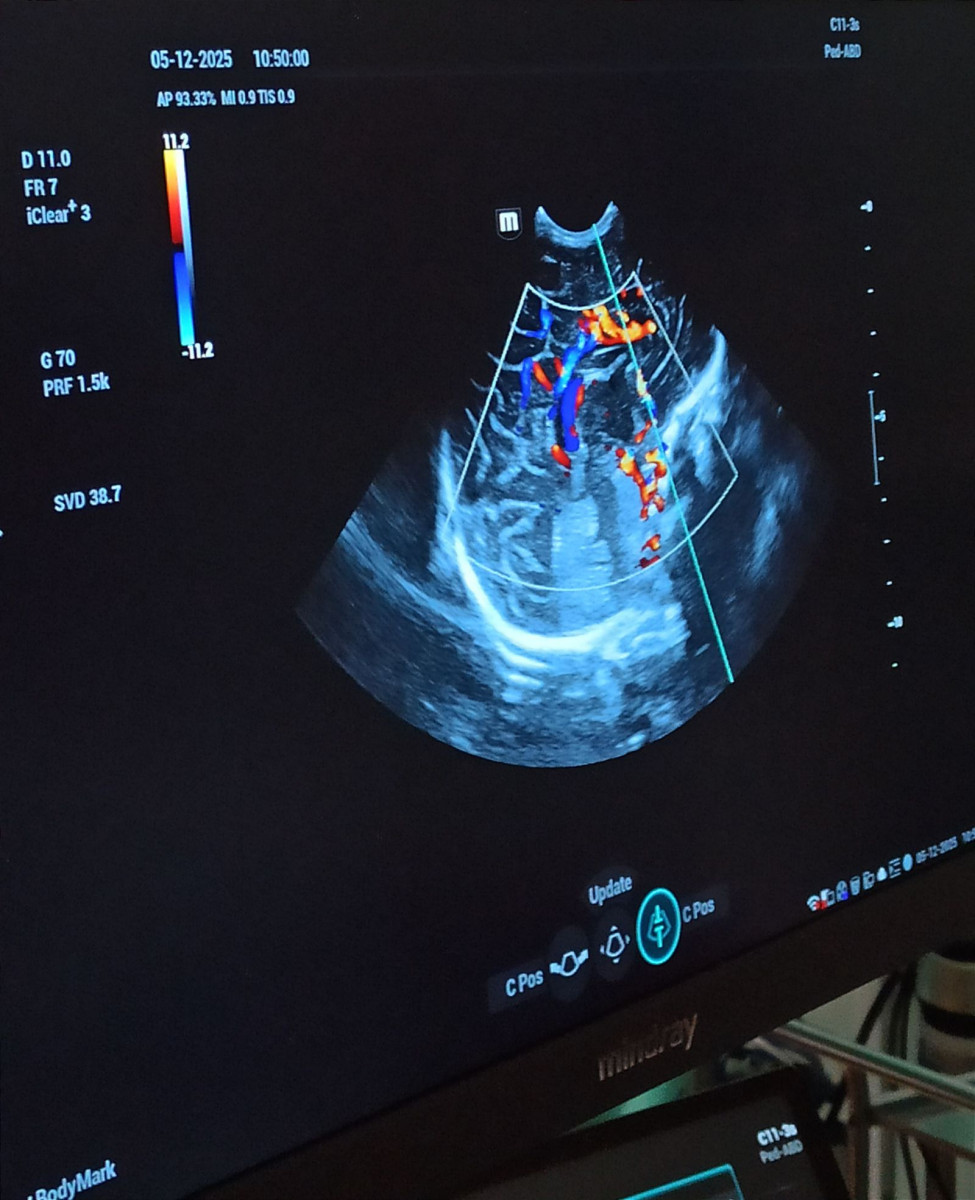

To zdecydowanie lepszy sprzęt niż ten, którym dysponowaliśmy wcześniej. Ma cztery specjalistyczne głowice przeznaczone tylko do badań noworodków do echo serca, badania główki, jamy brzusznej i stawów biodrowych. Jest też świetny program naczyniowy, którego używamy przy obrazowaniu naczyń mózgu, jamy brzusznej i serca - podkreśla Wojciech Kowalik.